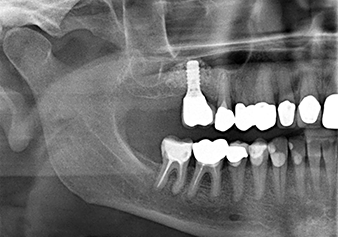

A 49-year-old female patient, a non-smoker and with nothing remarkable in her general medical history, was referred to our oral surgery practice for surgical extraction of tooth 16 and subsequent implantation. After the extraction, the patient experienced mild sinusitis trouble with the resultthat we initially waited six months before carrying out the measure. The residual bone height at the planned implant position measured 3-4 mm (Fig. 1 and 2).

To move the augmentation material in the direction of the maxillary sinus atraumatically, the implant was inserted very slowly by hand (Fig. 9). In the process, the membrane was pushed in the cranial direction once again. After two months, the surgical site healed without irritation. Six months later, the x-ray check showed a significant increase in opacity as an indication of ossification (Fig. 10). The prosthetic restoration was carried out with a metal-ceramic crown.